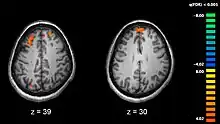

Imaginile de rezonanță magnetică funcțională (fMRI) și alte tehnologii de a obține imagini ale creierului permit studierea diferențelor de activitate cerebrală la persoanele diagnosticate. Imaginea prezintă două nivele ale creierului, cu arii (colorate în roșu) care sunt mai active în persoanele de control (sănătoase, imaginea din stânga) decât la suferinzii de schizofrenie (imaginea din dreapta). Imaginea provine dintr-un studiu cu fMRI a memoriei de lucru.[67]

Schizofrenia este corelată cu diferențe subtile ale structurilor cerebrale, prezente în 40-50% din cazuri și de chimie cerebrală, în timpul stărilor psihotice acute.[8] Studii care folosesc teste neuropsihologice și tehnologii de obținere a imaginilor creierului, cum ar fi fMRI și PET pentru a examina diferențele de activitate cerebrală au arătat că diferențele care apar în mod obișnuit sunt în lobii frontali, hippocampus și lobii temporali.[68] Reduceri ale volumului creierului, mai mici decât cele observate în cazul bolii lui Alzheimer au fost raportate în zonele cortexului frontal și lobilor temporali. Este însă nesigur dacă aceste schimbări de volum sunt treptate sau preexistente apariției bolii.[69] Aceste diferențe au fost asociate cu deficiențe neurocognitive care sunt corelate schizofreniei.[70] Deoarece circuitele neurale sunt afectate, s-a sugerat alternativa că schizofrenia trebuie gândită drept o asociere de tulburări de dezvoltare neurologică.[71]